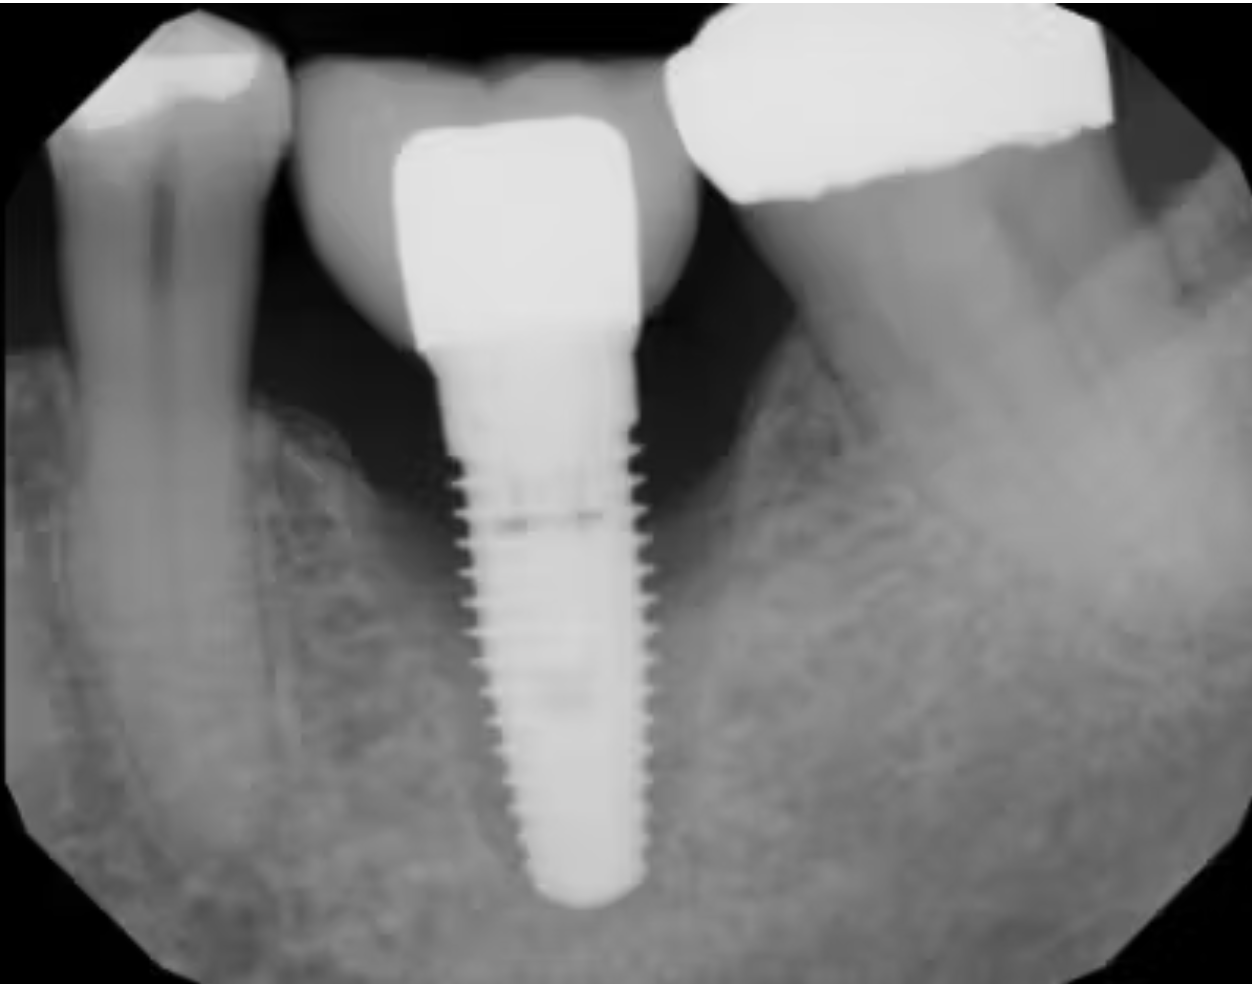

(Hình 1: Hình X-quang cho thấy mất tích hợp hoàn toàn và hiện tượng bao xơ)